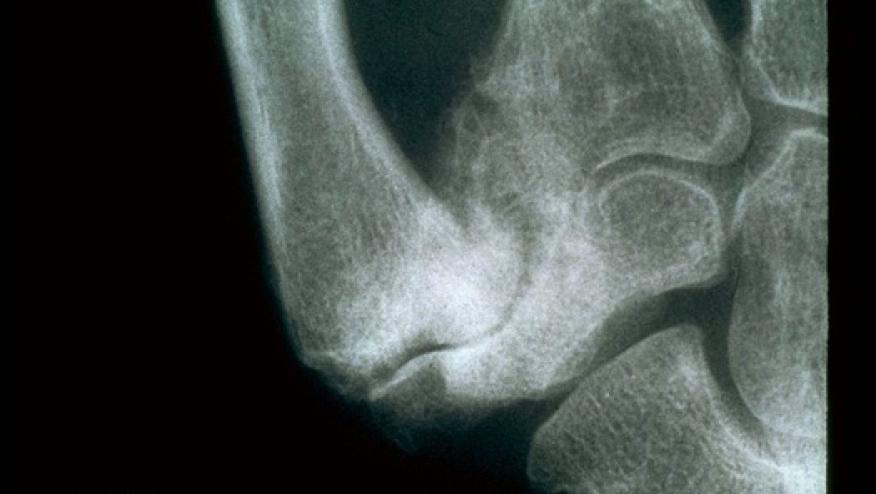

A randomized clinical trial of patients with CMC1 osteoarthritis shows modest benefits when a combination of conservative treatments (education, splinting, hand exercises, 1% diclofenac sodium gel) was used compared to education alone. While there were small to medium benefits with regard to hand function, there was no benefit in pain outcomes.

This Australian study included 204 CMC1 OA patients who were given either education alone or a conservative multimodal combination of therapies for 12 weeks. Hand function (Functional Index for Hand Osteoarthritis; 0-30) and pain (visual analog scale; 0-100 mm) were measured at week 6 (primary time point) and week 12.